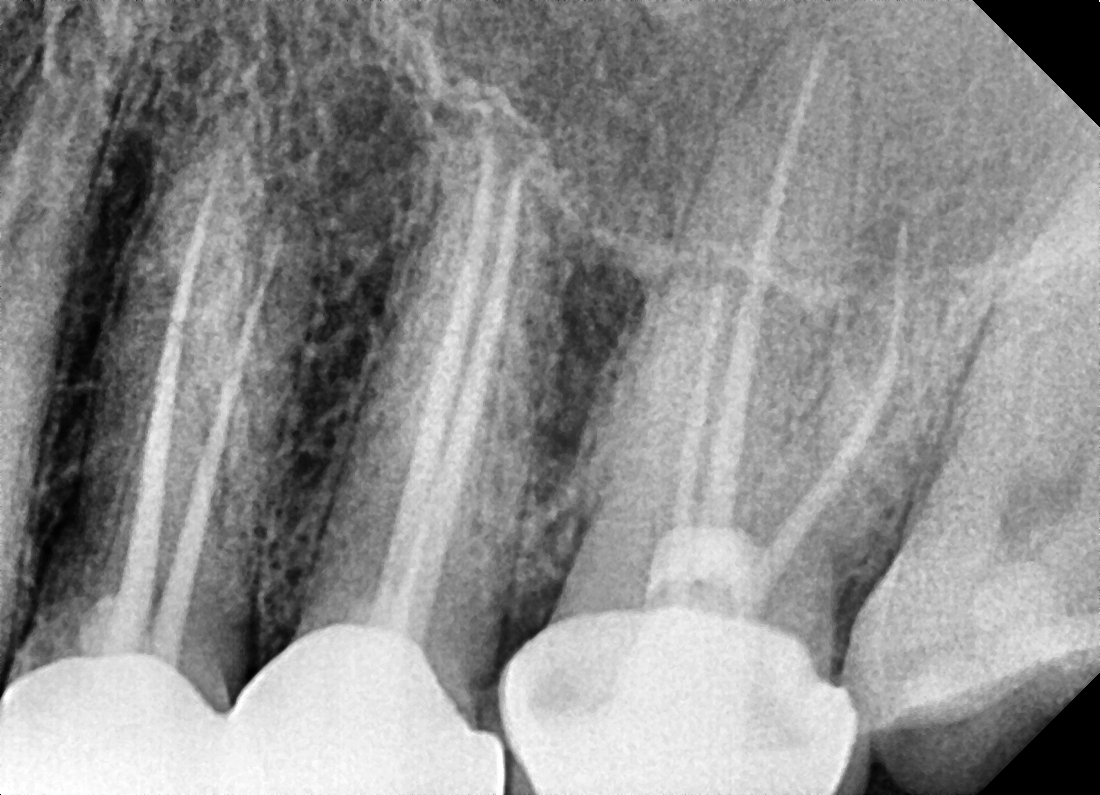

• A diagnosis is made for the tooth with percussion, palpation and cold tests and an x-ray.

• Measurements of the length of the root canal is noted and take x-rays to confirm the length. Ensuring that the entire length of the root canal is cleaned.